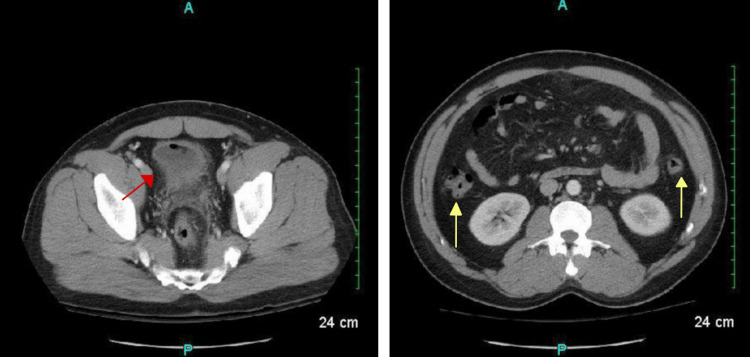

Computed tomography of the abdomen and pelvis with intravenous (IV) contrast demonstrated pockets of free air in the midline anterior abdominal wall and peritoneal cavity. (Figure 1).

There was also an air pocket tracking toward the liver margin with mesenteric induration and thickening, suggesting possible perforation. There was no free fluid, phlegmon, or fluid collections representing an abscess. The sigmoid colon revealed inflammatory changes along with the presence of scattered diverticula and colonic wall thickening, making the diagnosis of acute diverticulitis likely (Figure 2).

Additional pockets of air and an irregular hyper-dense nodular material were found in the anterior bladder along with diffuse urinary bladder wall thickening, suggestive of a CVF (Figure 3).